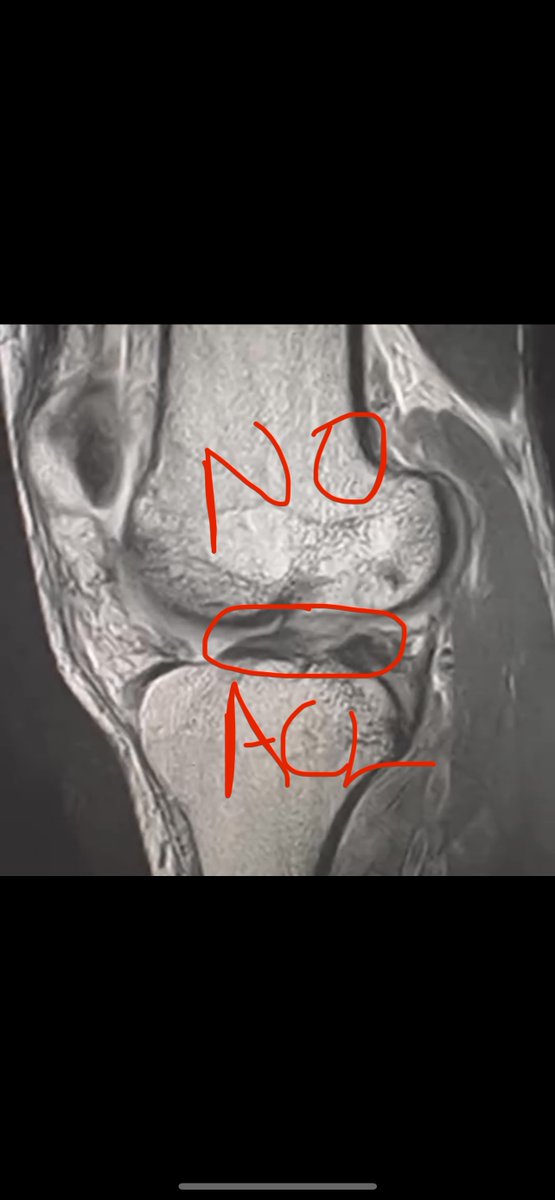

ACL Tears Can Heal WITHOUT SURGERY?! 🤯😱 In ~6 months time my client Michael achieved MRI verified ligament re-attachment as shown below 🧵

In ~6 months time my client Michael achieved MRI verified ligament re-attachment as shown below 🧵

MRI comparison of my client Michael 6 months post Grade III ACL Tear. MRI verified 50% healing of his ACL🔥 This *ALSO* coincided with IMPROVED function: 1.) Plyometrics 👟 2.) Heavy Squatting 🏋️‍♂️ 3.) Full Court Basketball 🏀 Not all cases reach this point but a lot do.

MRI verified 50% healing of his ACL🔥